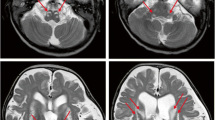

Patient 1, a 5-year-old boy, was born in a Chinese family with no family history of hereditary metabolic disease, with weighing 20 Kg, head circumference 52 cm and height 113 cm (Fig. 1A). He was G1P1 with a full-term normal delivery, and weighed 4000 g at birth. The patient frequently caught colds before the age of one and was admitted to the hospital at one and a half years old. Between the ages of 2 and 3 years, the patient’s feet were prone to peeling, and the symptom was relieved after vitamin B treatment. At 3 years and 10 months, the patient was readmitted with a high fever, weakness, and an inability to stand. The brain MRI diagnosed encephalitis. At 4 years, the patient’s brain MRI showed bilateral caudate nucleus and putamen nucleus were symmetrically swollen, and high diffusion weighted imaging (DWI) signal. (Fig. 1B) At 4 and a half years old, the patient experienced intermittent convulsions of both upper limbs, head, and face, and electroencephalography showed abnormal brain-wave activity. The patient’s brain MRI showed long T1 and T2 signals in the bilateral caudate nucleus and putamen nucleus, bilateral basal ganglia atrophy and brain sulci enlargement. Laboratory examination showed normal blood ammonia level (32 µM, normal range 18–60 µM). Whole exome sequencing (WES) and mitochondrial genomic sequencing were carried out to identify the disease-causing gene mutation. Following filtering with established criteria, two site variants (c.2090G > A and c.2122G > A) in the IARS2 gene were found, and no clinically significant mitochondrial genomic-related variants were observed. Segregation analysis confirmed that c.2090G > A from the patient’s mother and c.2122G > A from the patient’s father (Fig. 1C).

Family pedigree analysis, brain MRI images and variant analysis of IARS2. A. Pedigree analysis of patient 1 and patient 2 from two unrelated Chinese families. Rectangles indicated males, circles female, solid circle rectangled the affected individuals and probands were pointed out by arrows. B. Brain MRI images of patient 1 and 2. The patient 1 on the left showed lesions in the thalamus, periaqueductal, cerebellum and pons when he was 4 years old. The arrow pointed to the high signal were diseased areas. The patient 2 on the right showed long T1 and T2 signals in the lateral caudate nucleus and putamen, reduced cerebral white matter, bilateral basal ganglia symmetry damage, and cerebral dysplasia. The circled pointed to the symmetrical patchy were diseased areas. C. Sequencing chromatograms of IARS2 in patients and their parents. The arrows indicated the mutation sites. D. Quantitative analysis results of IARS2 in patient 2 and his parents

Patient 2, a 4-year-old boy, was born in a Chinese family with healthy parents (Fig. 1A). He was G3P3 with an abdominal delivery, and weighed 4350 g at birth. The child was admitted to the hospital at one and a half years old, weighing 13 kg, with a head circumference of 46 cm and a height of 73 cm. He couldn’t speak and had been diagnosed with growth retardation. It was hard for him to sit stably, and he was unable to walk or eat alone. The patient was readmitted at age 3 and diagnosed with dystonia and neurodevelopmental delays. Laboratory examination showed increased blood lactate (6.24 mM, normal range 0.50–2.20 mM), β-hydroxybutyric acid (1.05 mM, normal range 0.02–0.27 mM), and creatine kinase (1854.59 U/L, normal range 50–319 U/L). Brain magnetic resonance imaging (MRI) revealed long T1 and T2 signals in the lateral caudate nucleus and putamen, reduced cerebral white matter, bilateral basal ganglia symmetry damage, and cerebral dysplasia (Fig. 1B). He was subsequently diagnosed with LS. After filtering with established criteria, WES and mitochondrial genomic sequencing did not detect potential disease-causing gene mutations. Subsequently, whole genome sequencing (WGS) was performed. Following filtering with established criteria, a novel site variant (c.2450G > A) and a deletion variant with 1 and 2 exons (c.1_390del, NC_000001.11: g.220267444_220269568del) in the IARS2 gene were found, and no clinically significant mitochondrial genomic-related variants were observed. Segregation analysis confirmed that c.2450G > A was from the patient’s mother and c.1_390del was from the patient’s father (Fig. 1C). As shown in Fig. 1D, heterozygous mutations in IARS2 exon 1 and 2 of the patient were found by CNV-Seq. Quantitative PCR results showed that the mRNA level of IARS2 exon 1 and 2 in the patient and his father were significantly decreased compared with both age-matched controls and the patient’s mother.